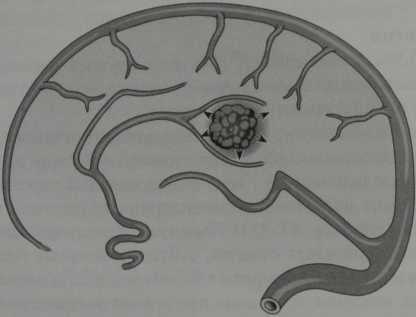

Кавернозная гемангиома (схематическое изображение). Дольковое расположение синусоидальных полостей с кровоизлияниями на разных стадиях распада. Гемангиома окружена ободком гемосидерина (стрелки).

- Центральный очаг может иметь гомогенный сигнал на Т1- и Т2-ВИ

- Структура по типу «тутовой ягоды», «медовых сот» или похожая на попкорн

- Может наблюдаться контрастное усиление гемангиомы

- Кровь на разных стадиях распада

- Перифокальный отек обычно встречается только при остром кровоизлиянии

- На Т2-ВИ обычно виден гипоинтенсив- ный ободок, соответствующий гемосидерину

- На Т2*-ВИ могут визуализироваться дополнительные, более мелкие кавернозные гемангиомы